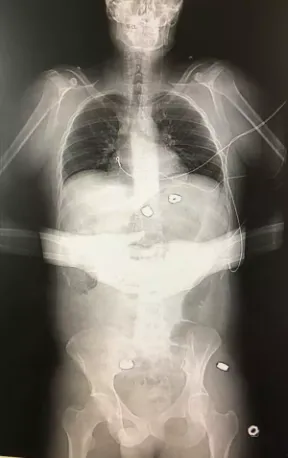

Strangely, although no such X-ray was contained in the medical evidence provided to the Court, one did appear in a LADbible report on the first anniversary of the Manchester Arena incident:

Hibbert told LADbible:

I had two seven-hour operations to remove the nuts and bolts. My feet, legs, arms and jaw were all smashed. One had severed my spinal column. My throat had a part missing. There was one bolt in my face they couldn’t get but it eventually rose to the surface and broke the skin itself. I tweezered it out. I keep it in a jar.

Yet, there is no obvious damage to the arms, throat, or jaw, or of shrapnel embedded in the face, in the above X ray. Nor is the image time-stamped, nor does it identify Martin Hibbert. Moreover, as Hall told the Court,

It cannot be deduced from the X ray, without a lateral view, whether the alleged shrapnel is inside the body, or not. The shrapnel could be on top of the body, underneath the body or possibly even using computer software.

In sum, there is no reason to trust the authenticity of the image.

Tellingly, the claimants did not enter the LADbible X-ray into evidence. They must have known that it would not withstand scrutiny. In which case, why did Martin Hibbert authorise its usage in the first place?